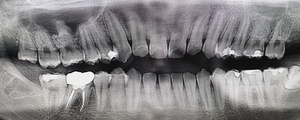

Before(下親知らずの抜歯前) 横に生えた状態で埋まっている親知らず 虫歯がある親知らず 抜歯前の骨の状態のレントゲン像

After(下親知らずの抜歯後) 横に生えた状態で埋まっている親知らずの抜歯後 虫歯がある親知らずの抜歯後 抜歯後の骨の状態のレントゲン像

原因をより詳しく調べるためレントゲンを撮影したところ、右下の親知らずは骨の中に埋まった状態のまま真横に生えて隣接する歯を押しており、前方の歯が虫歯になっています。 そのため、右下の親知らずと隣の奥歯の間には、歯と歯ぐきの境目の溝である「歯周ポケット」が通常よりもかなり深くなっていました。

まず、親知らずと骨の中にある神経の位置、歯や周囲の骨の詳細な情報を確認するために、歯科用パノラマデジタル写真で口腔内を撮影します。撮影結果を踏まえ、抜歯方法や施術の難易度をしっかり確認しました。

1年後、取り除いた親知らず周囲の骨がしっかり再生したことを確認しました。